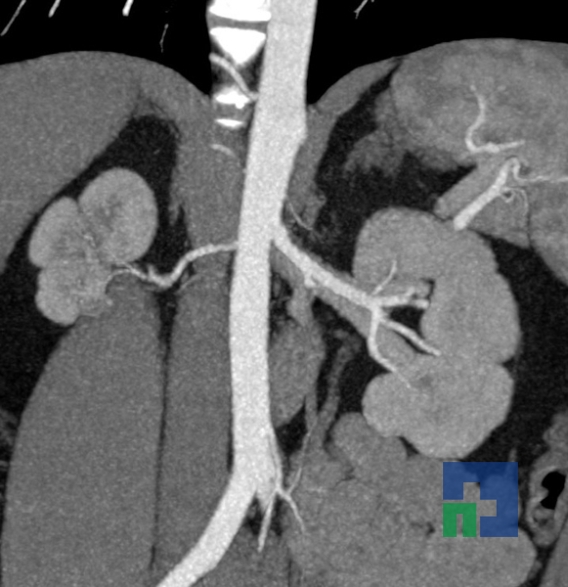

- Accidentelor vasculare cerebrale ischemice sau hemoragice